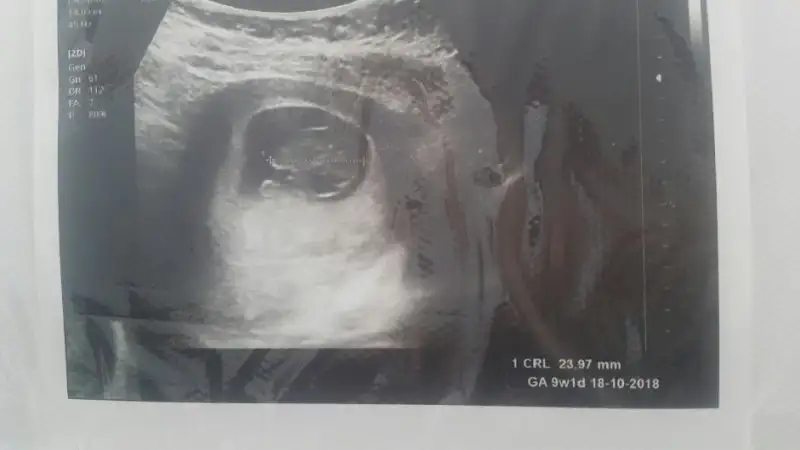

dün doktora gittik çok şükür herşey yolundaydı, hatta ufak bir hareket bile çekti bizim minik. 3 hafta sonra 2li için çağırdı doktorumuz.

Teoriye göre cinsiyet tahmini alabilir miyim ben de sizden :emir_bebek::)

• 2018-03-17 18.01.15.webp

2018-03-17 18.01.15.webp

11 KB · Görüntüleme: 76

• 2018-03-17 18.00.37.webp

2018-03-17 18.00.37.webp

9,5 KB · Görüntüleme: 77

Erkek diyorum :) 1 aya artik tum derdimiz cinsiyet olur insallah topikce :) netlesti mi netlesmedi mi heyecan yapalim :)